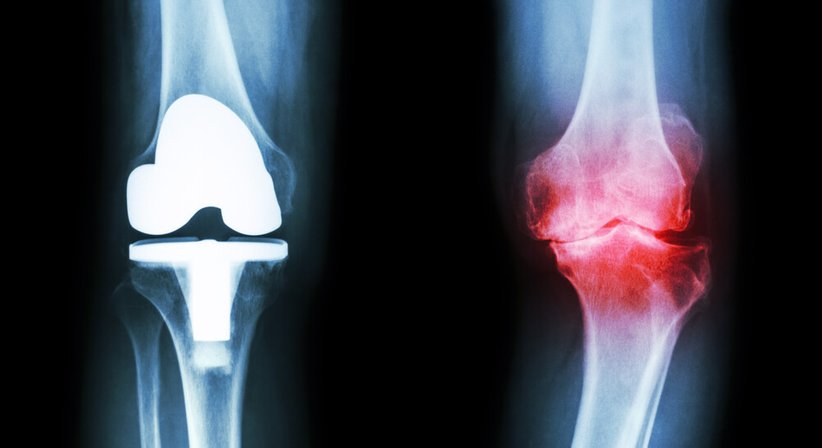

Die Gonarthrose ist eine typische Abnutzungs- bzw. Verschleißerscheinung, die sich meist langsam und schleichend entwickelt. Sie kann aufgrund bestimmter Risikofaktoren (u.a. starkes Übergewicht, Beinachsenfehlstellung, Verletzungen des Kniegelenks) auch schon bei jüngeren Menschen entstehen.

Die Behandlung einer Gonarthrose richtet sich nach dem Schweregrad der Beschwerden und kann sowohl konservativ als auch operativ (künstlicher Gelenkersatz) erfolgen.